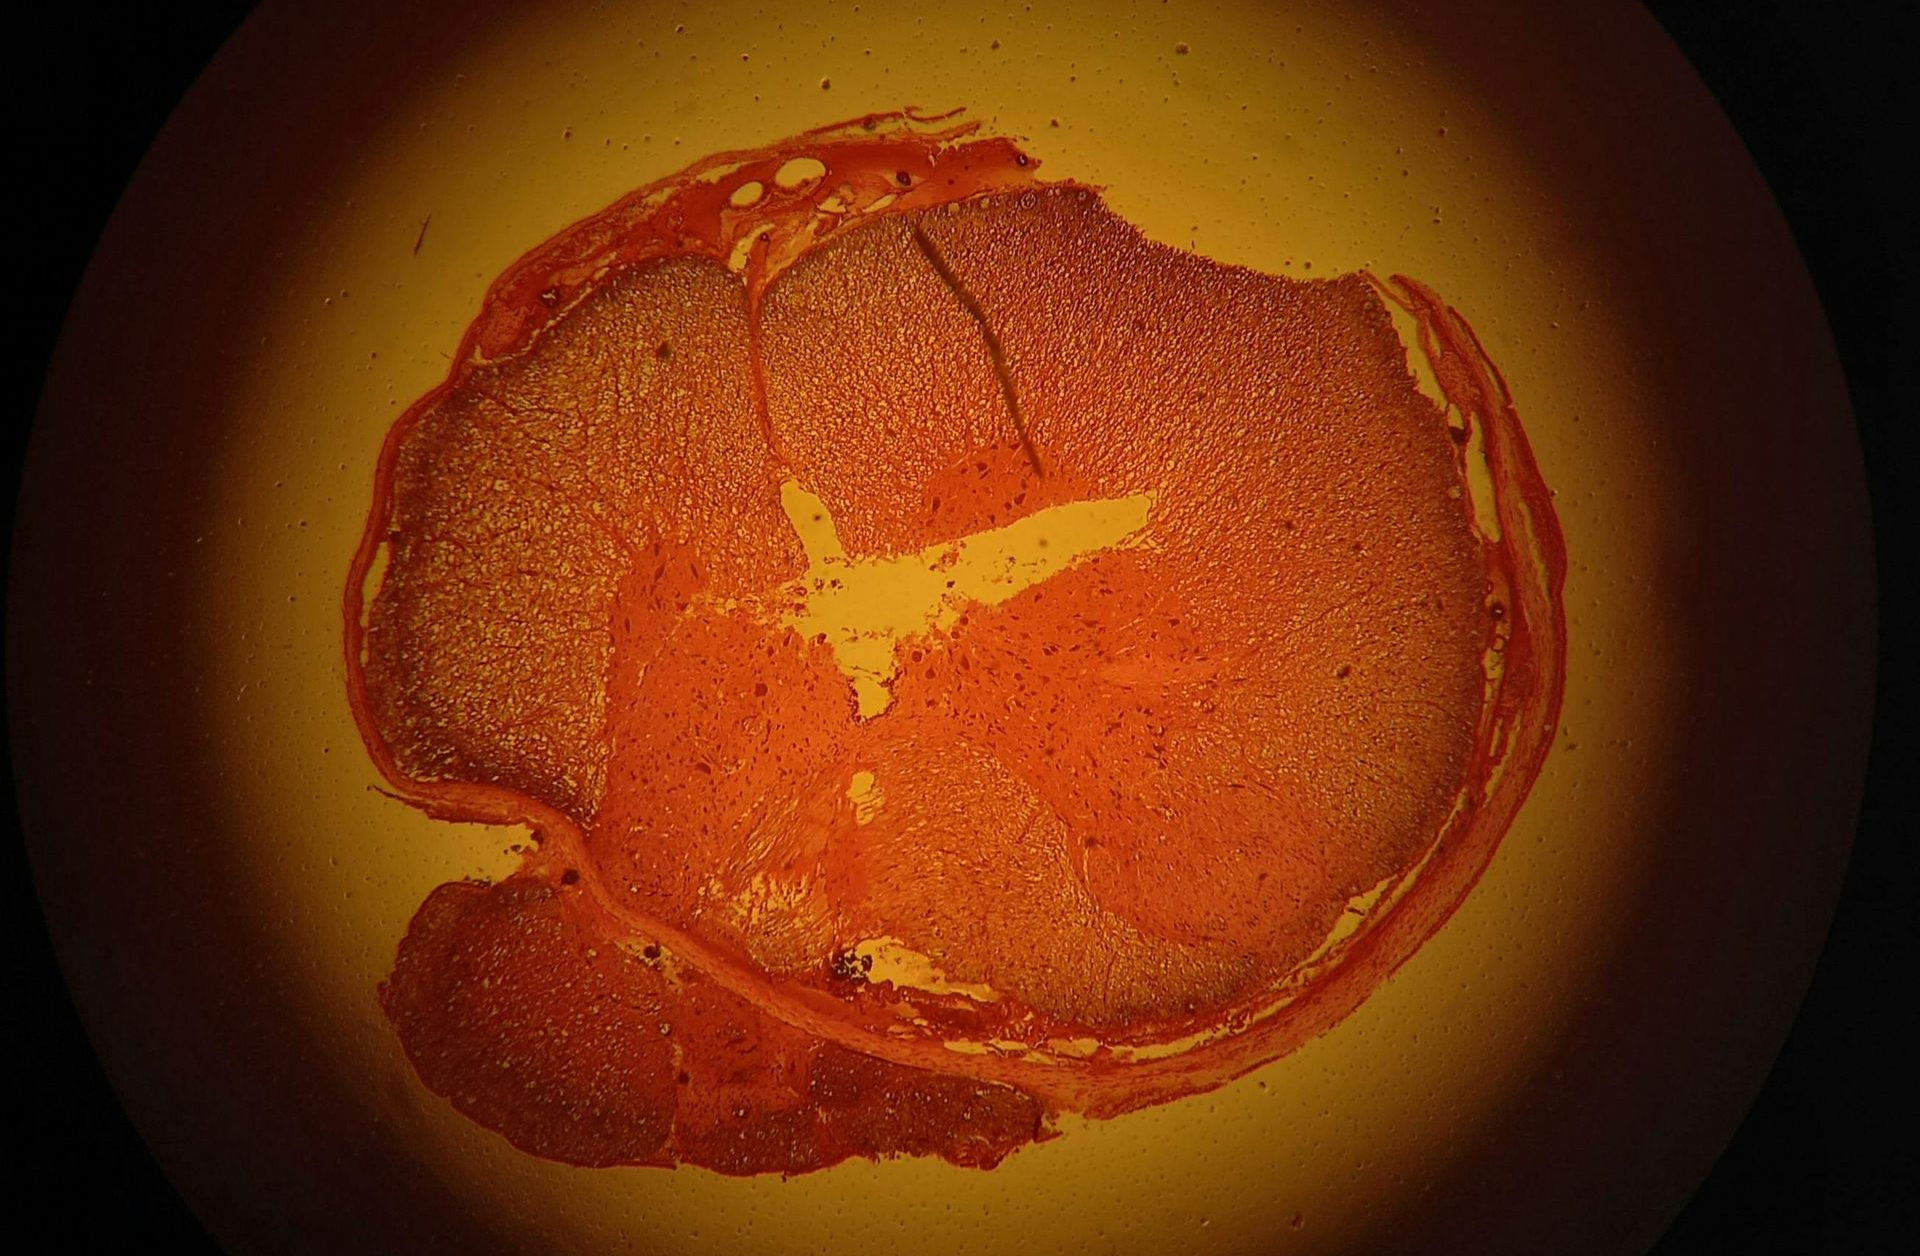

Visual searching has a method: a series of spotlight sweeps that go across the visual field. Our fovea, the centre of our vision, can only cover a very small area roughly the size of a thumbnail at arm’s length. This “spotlight” sweeps over a scene gathering detail, sacrificing everything outside its purview. Our eyes will also jump across a scene, by saccades, to cover large areas. These pursuit and saccade movements are constantly and unconsciously being performed by our eyes.

The part of the brain that is crucial to spatial awareness and directing attention is called the parietal lobe. The pathway that runs to this lobe from the eyes is called the dorsal stream. The parietal lobe allows us to see where objects are in space and plays a crucial role in guiding attention during visual search. In the gorilla video, the larger jumps that our eyes perform to track the balls, the saccades, play a part in reducing our attention. This is good when we really want to focus on something yet may be a deadly problem when we are multitasking in say, heavy traffic or when we are texting and driving.